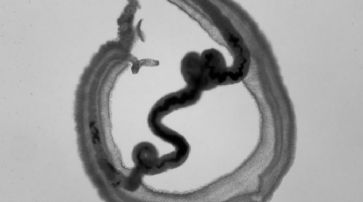

Biomed-Kamera löst teures Standard-Mikroskop ab

Boston - MIT-Forscher haben ein biomedizinisches Fotosystem entwickelt, welches die Kosten des Labor-Equipments in diesem Bereich von 100'000 Dollar auf wenige hundert Dollar herunterschrauben kann.

Die technische Anordnung kann in der Krebsdiagnose und in der DNA-Sequenzierung zur Anwendung kommen. In klinischer Praxis nutzbar

Laut den Wissenschaftlern ist das neue System sowohl für die klinische Praxis als auch für die biologische Forschung geeignet. "Das Ziel unserer Arbeit ist es, die elektronische und optische Präzision von sündhaft teuren Mikroskopen durch elegante mathematische Modelle zu ersetzen", unterstreicht Ayush Bhandari, einer der Entwickler des revolutionären Ansatzes.

Mini-Mikroskope dienen zur Diagnose von Parasiten